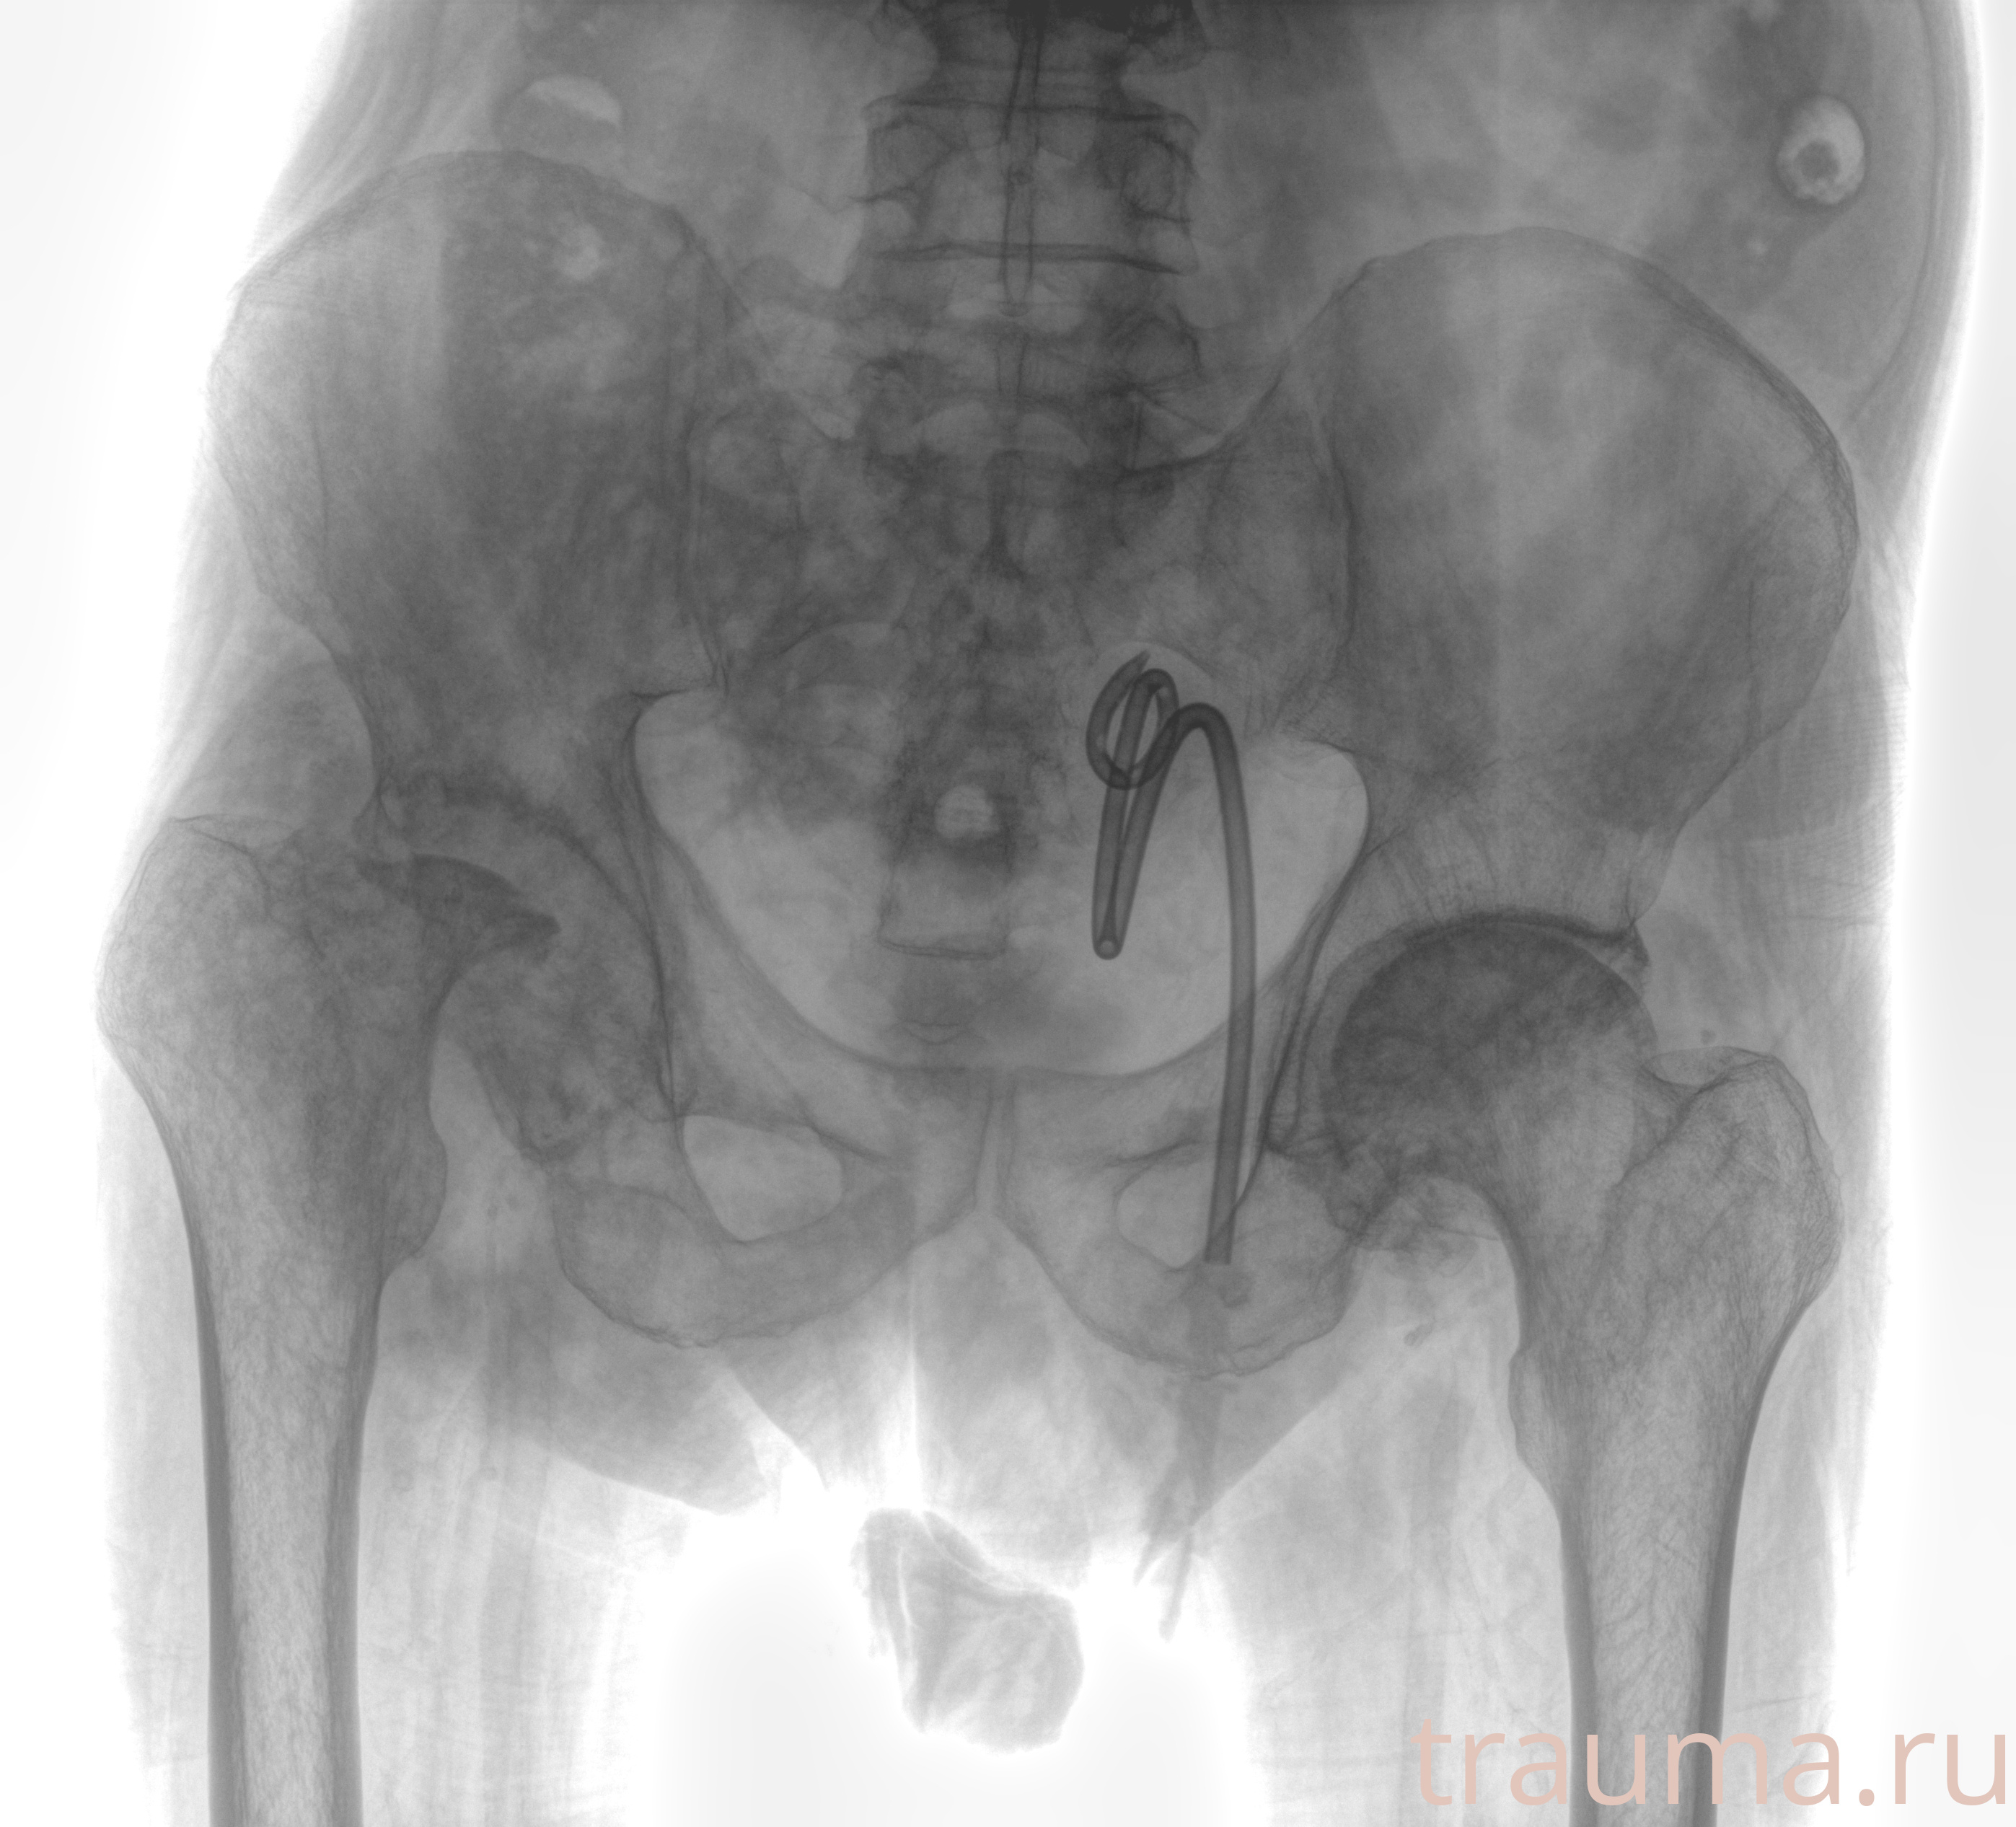

Рентгенограммы

Рентген на дому: по вашему адресу приезжает врач-рентгенолог, травматолог-ортопед с мобильным рентгеновским аппаратом, проводит диагностику травмы или заболевания, делает необходимые рентгенограммы, дает рекомендации по дальнейшему лечению. Получить качественные снимки в домашних условиях возможно благодаря уникальной методике, разработанной МосРентген Центром для института  Склифосовского